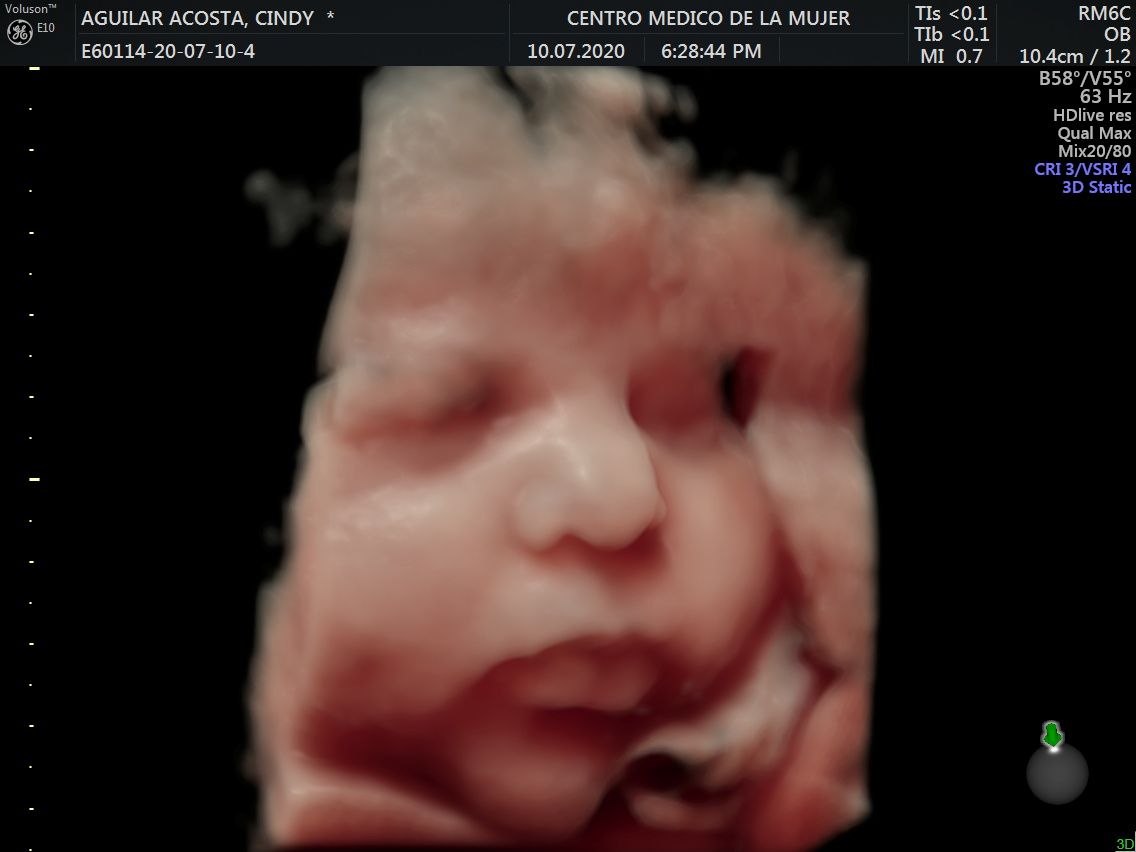

Fotos y videos

ECO Anatómico

Consiste en la evaluación especifica de cada organo y sistema del bebé con medidas detalladas de cada parte para evaluar su crecimiento proporcional.